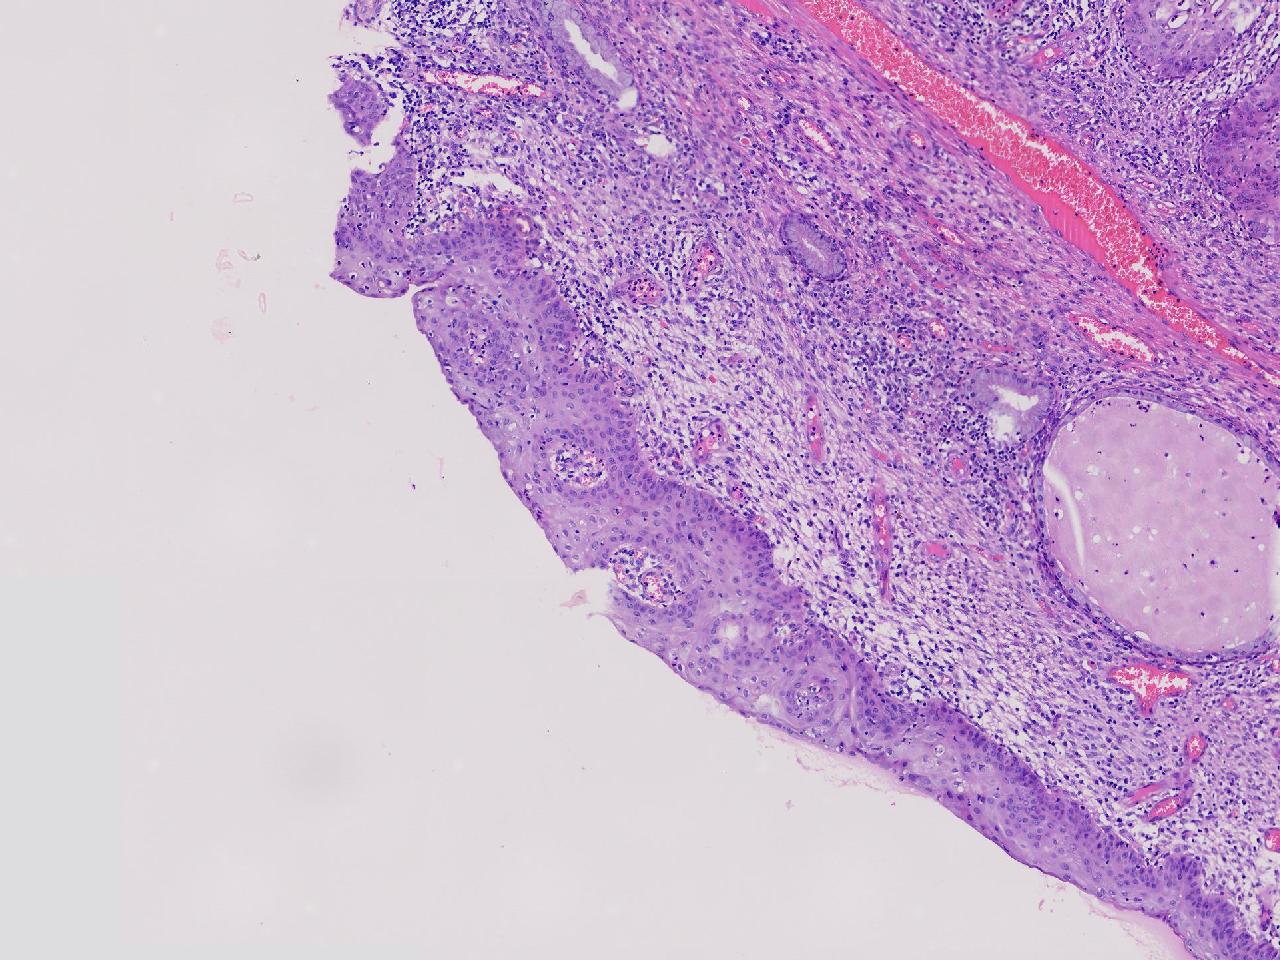

性别年龄42岁临床诊断宫颈赘生物

一般病史女,42岁,妇检时发现宫颈赘生物,大小0.2cmx0.5cm

标本名称管状赘生物

大体所见灰白色不整形软组织2块,一个直径0.3厘米,一个直径0.2厘米。

炎症

低级别诊断需要有个尺子,这个尺子就是“似是而非为非”,这个连似是而非都达不到。

有非典型鳞化,建议HPV检测

慢性宫颈炎伴腺上皮鳞化。